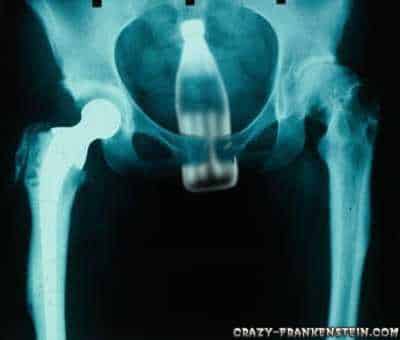

5. Une bouteille

Certains et certaines prennent de la bouteille.